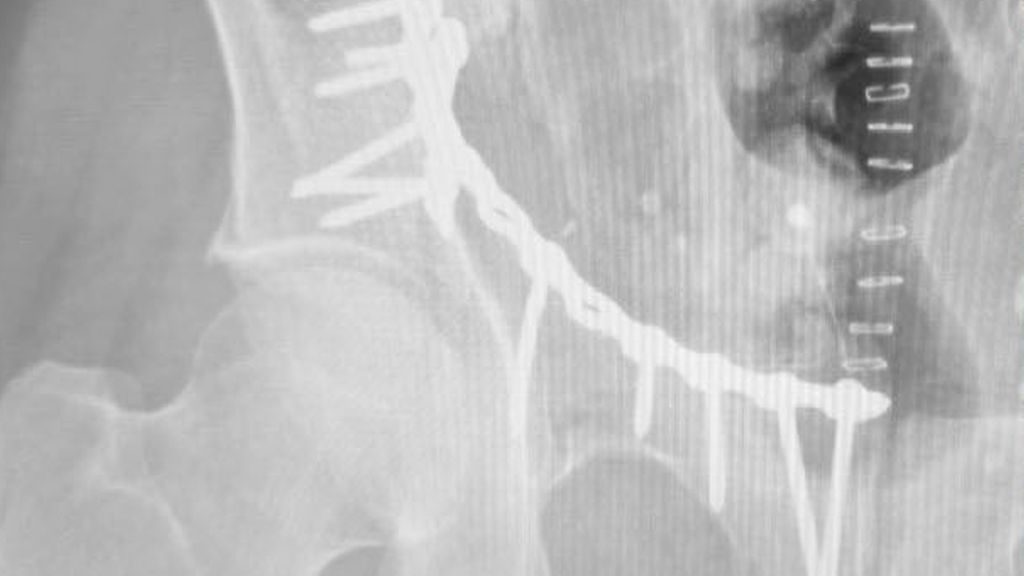

Das nächste Ziel war die Universitätsklinik Innsbruck. Die Lage zwischen den Bergen ist jedes Mal aufs Neue besonders beeindruckend. In Innsbruck hatte ich die Möglichkeit, mit Klinikleiter Prim. Univ.-Prof. Dr. Rohit Arora und Assoz. Prof. PD Dr. Dietmar Krappinger einen abwechslungsreichen OP-Tag zu erleben. Neben einer anspruchsvollen Beckenversorgung konnte ich auch Fällen aus der Handchirurgie und der Endoprothetik beiwohnen. Auch hier gab es wieder die Möglichkeit des fachlichen und persönlichen Austauschs mit den Kolleg:innen bei einem entspannten Abendessen. Am Donnerstag hatte ich erneut die Gelegenheit, Prof. Arora in den OP zu begleiten. Nach einer periprothetischen Frakturverplattung durfte ich bei der Versorgung einer komplexen suprakondylären Humerusfraktur mitwirken – danach hieß es schon wieder Abschied nehmen.

Von links nach rechts: Feldkirch, Innsbruck (Beckenverplattung), St.Johann i.T., Zell am See, Salzburg